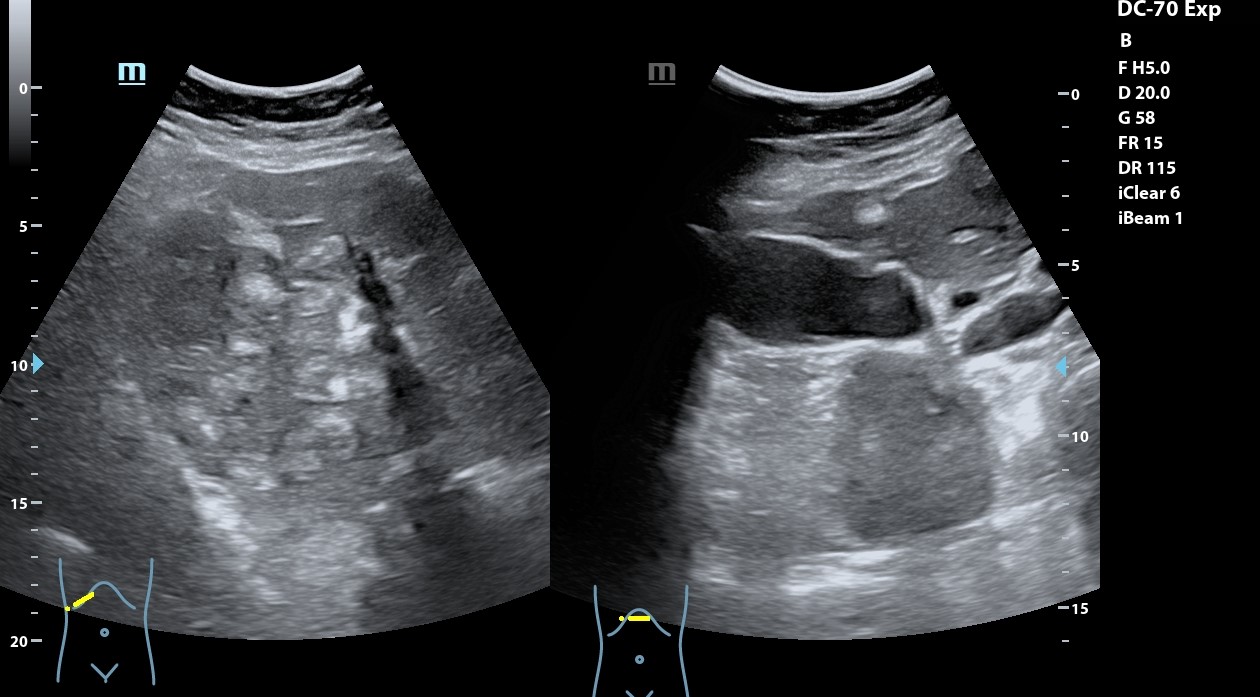

Hígado con abundantes LoEs hiperecogénicas con halo hipoecogénico. Retroperitoneo con abundantes imágenes redondeadas, hipoecogénicas peripancreáticas y retroperitoneales que llegan a medir 28 mm. A nivel de fosa ilíaca izquierda se observa imagen en pseudoriñón que con Doppler presenta captación y llega a medir hasta 72,2 mm.